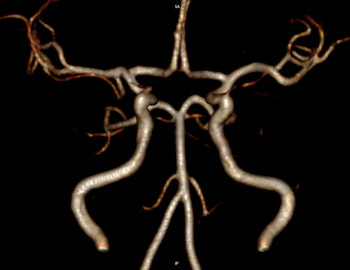

最初に問診を行います。必要に応じて検査を行い、その後、診察/検査結果を説明し方針を立てます。脳神経外科診療においてはMRI検査が頭蓋内評価に有用ですので、診察/診断の根拠のためにもキー写真をスナップショットでお渡しするようにしております。

既に脳梗塞など患った患者に対し、今後の予防や症状悪化を防ぐため生活習慣病指導を行います【理念1・2】。また、必要に応じ麻痺の維持改善目的で経頭蓋磁気刺激療法を積極的に取り入れております。【理念1】。

さらに生活習慣病に対して追加治療が必要な場合は、専門機関への医療連携を行っております【理念5】。